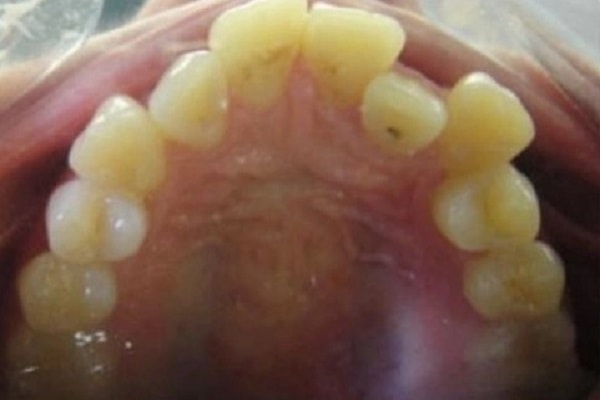

The ideal age for braces is 12 or 13 years old, when a child's mouth and jaw are still growing. Treatment can also start at an earlier or later age, depending on needs.

Orthodontic treatment using braces can usually start by the age of 12, after most of the permanent teeth have erupted. However, some children can start as young as 10 years old and there are specialized treatments targeted even for children as young as six years old, such as Invisalign First.

Many patients start between the ages of 10 and 14, orthodontic assessments at routine check-ups will help determine the right time. While there are some advantages to early treatment, successful results can be achieved with braces at any age. The orthodontist decides exactly when orthodontic treatment should begin after evaluating the individual's specific needs and growth pattern.